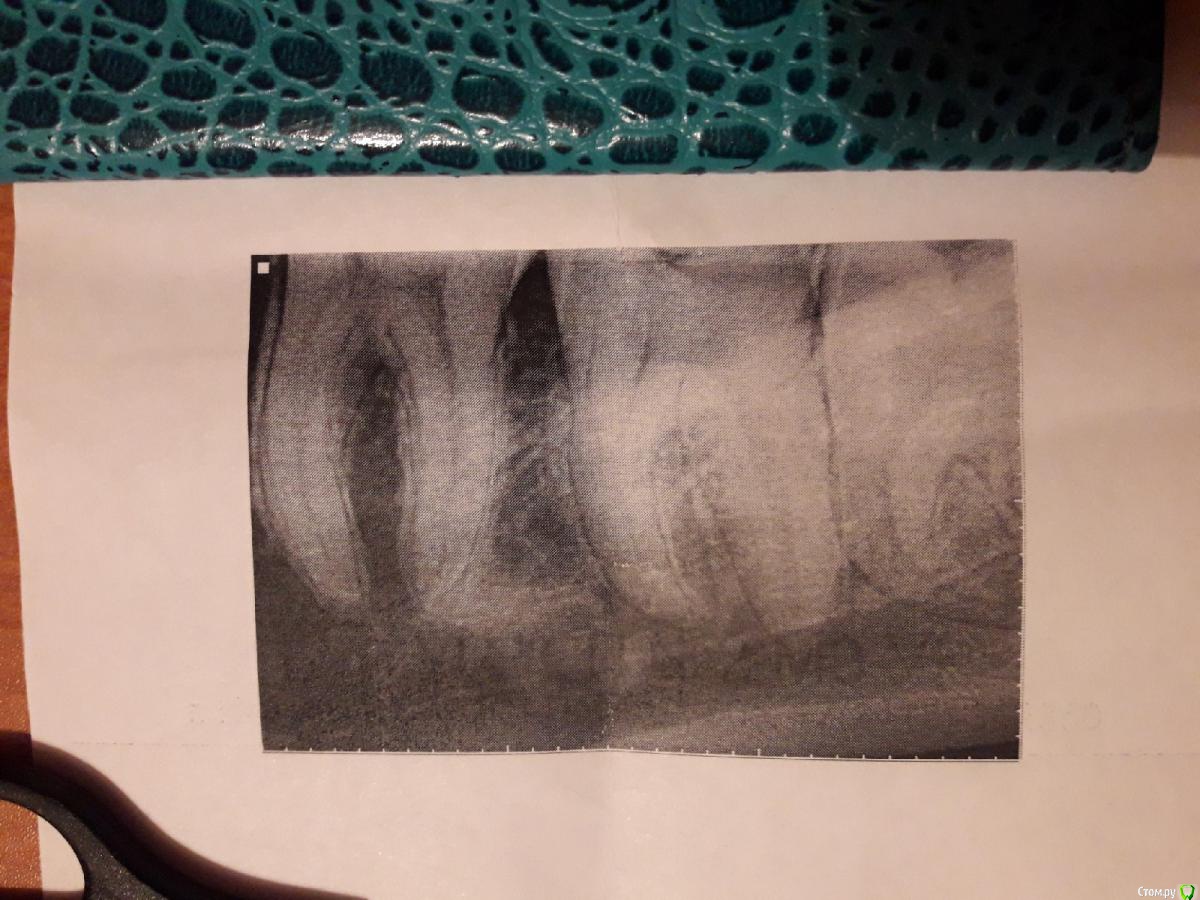

kotya2015 Опубликовано 29 октября, 2019 Поделиться Опубликовано 29 октября, 2019 Здравствуйте, уже как месяц появились ноющие боли в косточке под зубами, в районе 6 и 7 зуба. Слабая боль, иногда отдает в ухо. На осмотре была у двух стоматологов, внешне проблемы они не нашли. Зубы не больно при жевании, при постукивании тоже. Десна не воспалена. В 6 и 7 стоят пломбы.Сделала снимки зубов. Подскажите пожалуйста есть ли какие то проблемы на снимках?Что можете вызывать такую боль? Ссылка на комментарий

kotya2015 Опубликовано 6 ноября, 2019 Автор Поделиться Опубликовано 6 ноября, 2019 Делайте томограмму и выкладывайте исследованме и срезы.Здравствуйте. Сделала кт. И нашли какой то белый сгусток. Что это может быть такое? Ссылка на комментарий

kotya2015 Опубликовано 6 ноября, 2019 Автор Поделиться Опубликовано 6 ноября, 2019 Гиперостоз, нужны еще срезы этой области.Вот сделала еще.Гиперостоз это опухоль? Ссылка на комментарий

krokomot Опубликовано 6 ноября, 2019 Поделиться Опубликовано 6 ноября, 2019 Сложно сказать похоже на остеому. Но нужна динамика, есть ли рост, или она в таком состоянии много лет. В этом аком состоянии 8й зуб в полости рта, его коронка полностью видна? Ссылка на комментарий

kotya2015 Опубликовано 6 ноября, 2019 Автор Поделиться Опубликовано 6 ноября, 2019 Сложно сказать похоже на остеому. Но нужна динамика, есть ли рост, или она в таком состоянии много лет. В этом аком состоянии 8й зуб в полости рта, его коронка полностью видна?8 зуб почти прорезался, на кт вроде бы он последний. А насчет остеомы какой порядок действий при ее обнаружении. Наблюдение? И если ее удалять, удалять нужно вместе с зубом? Ссылка на комментарий